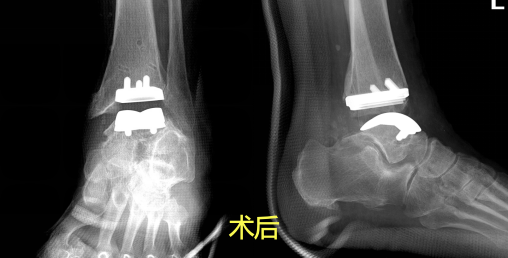

找准问题根源后,医生团队立刻调整治疗方案,经过反复综合评估,最终决定为阿姨实施踝关节置换手术,同时把断裂的韧带重新修复加固,一次性解决“关节磨损剧痛”和“脚踝晃不稳”两大难题。手术过程精准又顺利,医生顺利完成人工关节置入和韧带修复,术后该女士恢复状态特别好,目前已经顺利进入术后康复阶段,慢慢就能恢复正常行走。

终末期严重踝病:像这位女士一样,关节软骨彻底磨损的患者,通过踝关节置换手术重建关节功能,搭配韧带修复,让脚踝重新变灵活、变稳固。